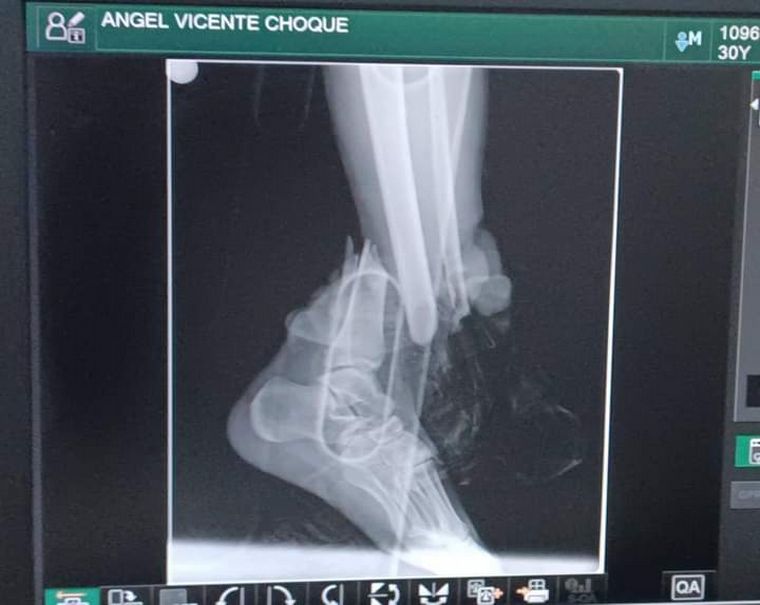

Un albañil argentino que había viajado a la ciudad boliviana de Cobija para trabajar fue atropellado por un motociclista -aparentemente alcoholizado- que le fracturó tibia y peroné. Desde el hospital donde Ángel Vicente Choque está siendo atendido le demandan $1,5 millón para una operación que necesita para iniciar la recuperación y no tiene el dinero.

El argentino fue derivado al Hospital Dr. Roberto Galindo Terán, al norte del país en una zona amazónica y cerca de la triple frontera con Brasil y Perú. Allí fue atendido en primeros auxilios y le instalaron unos fijadores de urgencia para evitar que perdiera la pierna. Por mantenerlo internado, la familia desembolsó más de $400.000, pero el monto final es mucho más alto.

Y añadió: "Mi hermano está esperando que consigamos el dinero para que él pueda entrar a la cirugía, se le coloque la placa y le saquen los soportes del pie izquierdo".